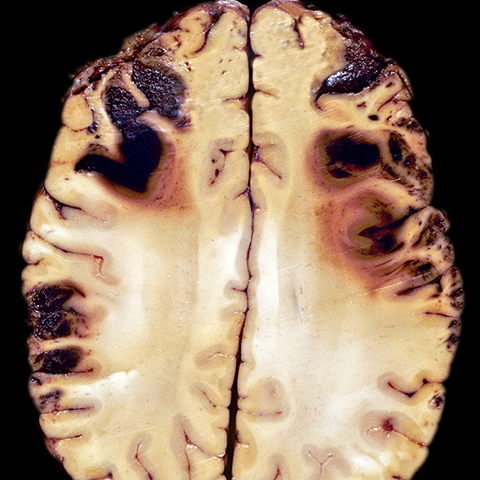

Fatal Head Trauma